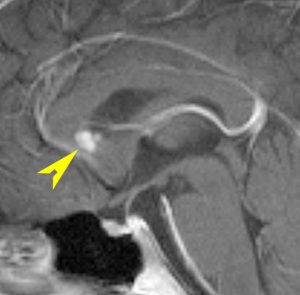

尿崩症にて発症した2年後にようやく小さなneurohypophyseal germinomaを発見された9歳女児例です。術前のT1強調画像では下垂体後葉のbrightnessが消失し,下垂体柄が腫大しています(左側)。ガドリニウムで腫瘍部分が増強されますが前葉よりは低信号となっています(右側)。経蝶形骨洞生検術で確定診断を得た後に,シスプラチンとエトポシドを1コース投与したところ腫瘍は完全消失しました。3コース後に24Gy12分割の放射線治療を加え再発はありません。残っていた下垂体前葉機能は治療後に少し改善しました。生検術では,トルコ鞍底を開けて下垂体後葉の下部を目標にして小さな組織採取をします。GHDがあっても前葉にはmassとしての腫瘍が無いと考えた方がいいでしょう。

この例は18歳,HCG 0.1mIU/ml,尿崩症で発症しました。神経下垂体ジャーミノーマなので,下垂体前葉のみが残って後葉から視床下部が腫瘍化しています。よくよく見ると松果体にもごく小さな腫瘍があります。右のCISS画像で松果体の腫瘍化が明瞭です。